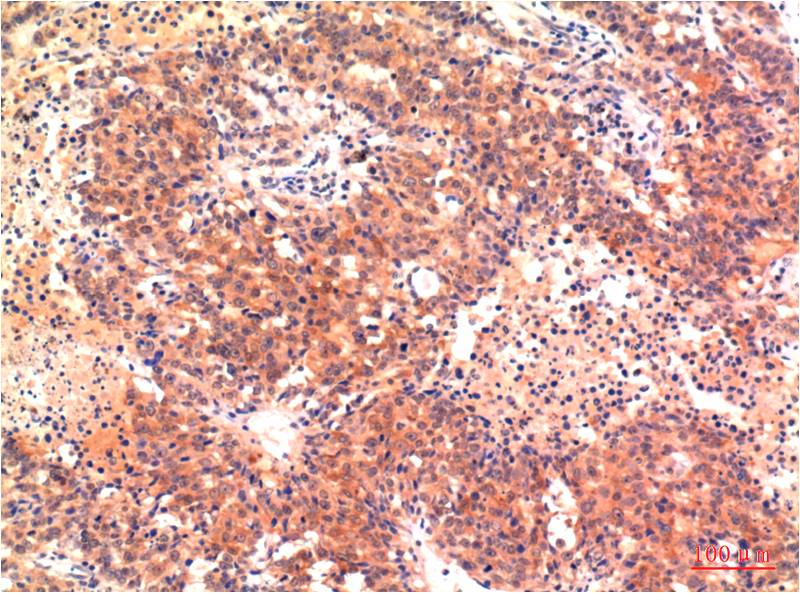

Immunohistochemistry analysis of paraffin-embedded Human Heptacarcinoma Tissue using LC3A antibody.High-pressure and temperature Sodium Citrate pH 6.0 was used for antigen retrieval.